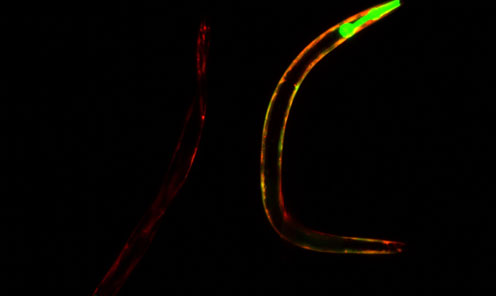

"Il nostro nuovo studio dimostra un calo del livello di NAD+ in funzione dell'età, e tale diminuzione è molto maggiore negli organismi con un invecchiamento precoce e con mancanza di riparazione del DNA. Siamo stati sorpresi di vedere che l'aggiunta di NAD+ ha sia rinviato i processi di invecchiamento delle cellule, che allungato la vita dei vermi e di un modello di topo", ha detto il professor Vilhelm Bohr dal Center for Healthy Aging e del National Institute of Health.

I ricercatori hanno allevato topi e nematodi con atassia telangiectasia (A-T) per lo studio. I pazienti di A-T hanno una degenerazione progressiva della parte del cervello responsabile del coordinamento, una riparazione carente del DNA, e altri sintomi caratteristici dell'invecchiamento precoce.